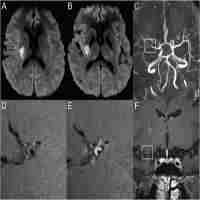

| Abstract | OBJECTIVE: To evaluate the characteristics of atherosclerotic middle cerebral artery (MCA) stenosis by high-resolution magnetic resonance imaging (HR-MRI) and determine the relationship between wall characteristics and infarction patterns. METHODS: Thirty-six patients with acute ischaemic stroke due to MCA stenosis underwent diffusion-weighted magnetic resonance imaging (DWI) and HR MRI. Wall characteristics of MCA, including irregular surface, superior location, T2-hyperintense of plaques and positive remodelling (PR), were analysed. Characteristics of acute infarct on DWI were categorised according to the number (single or multiple infarcts) and the pattern of cerebral infarcts (cortical, border zone or perforating artery territory infarcts). The relationship between wall characteristics and infarction patterns was evaluated. RESULTS: PR was observed in 20 patients, irregular surface plaque in 18 patients, superior location of plaques in 14 patients and T2-hyperintense foci in 13 patients. Seventeen patients had multiple acute cerebral infarcts and 13 showed single acute cerebral infarcts. Border zone infarcts were the most common (76.5%) among multiple acute infarcts. Penetrating artery infarcts (PAI) accounted for 76.9% of all single infarcts. Multiple infarcts were more frequently observed in patients with PR (P = 0.007) or plaque surface irregularity (P = 0.035). Single infarcts, especially PAI, were more prevalent in patients with superior plaque (P = 0.030). No statistically significant differences were observed between multiple and single infarcts in patients with T2-hyperintense lesions (P = 0.638). CONCLUSIONS: PR or irregular surface plaques were associated with artery-to-artery embolism. Superior location of plaques was associated with PAI. HR-MRI provides insights into intracranial atherosclerosis in vivo, predictive of infarction patterns. |